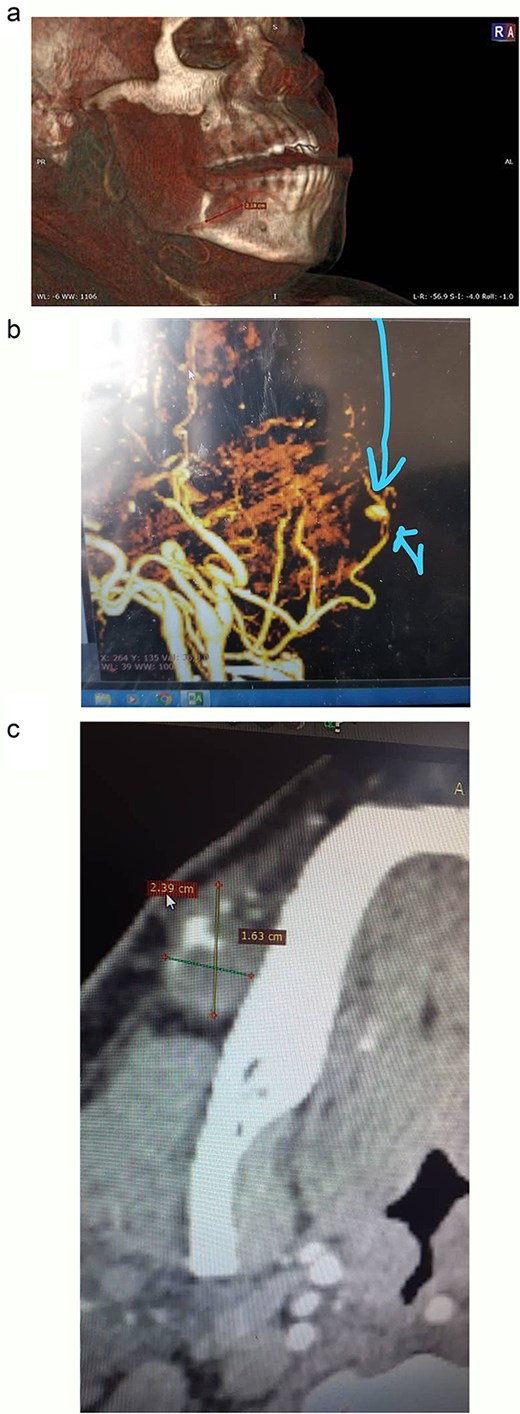

Doppler ultrasound of the mass revealed a 19 mm ovoid formation in the right hemi-mandibular region, with arterial waveforms and likely afferent and efferent arteries. Craniocervical computed tomography (CT) (Fig. 1a–c) confirmed a saccular aneurysm of the right facial artery, measuring 23.9 × 17 mm, thrombosed in two-thirds of its lumen.

CT images illustrating the right facial artery aneurysm: (a) 3D-reconstructed CT scan highlighting the aneurysm. (b) Preoperative contrast-enhanced CT with 3D reconstruction indicating the aneurysm. (c) Preoperative axial contrast-enhanced CT demonstrating the saccular aneurysm of the right facial artery and its measurements.